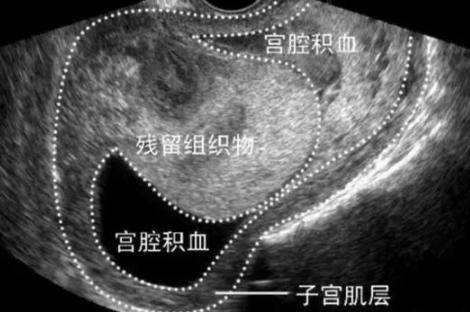

吉林国健妇产医院的专家介绍说,产妇可以根据产后恶露不同时期的不同性状自己观察,比如在分娩后2-3周出血量突然增多,甚至发生大出血,这就有可能是胎盘附着部位子宫复旧不良、胎盘胎膜或蜕膜残留、子宫切口感染,最好到医院检查一下,另外如果产后2个月恶露还没有彻底干净,也要到医院检查。